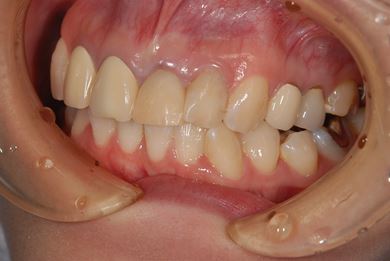

| 性別/年齢 | 女性 / 27歳 | ||||||||||||||||||||||||||||||||

| 主訴 | 審美歯科治療を希望。歯ならびもできるかぎりそろえたい。 | ||||||||||||||||||||||||||||||||

| 治療内容 | オールセラミック4本(オールセラミック用土台4本)、メタルボンドセラミック2本(メタルボンドセラミック用土台2本) | ||||||||||||||||||||||||||||||||

| 総治療費 | 867,825円 | ||||||||||||||||||||||||||||||||

| 治療期間 | 5ヶ月 |